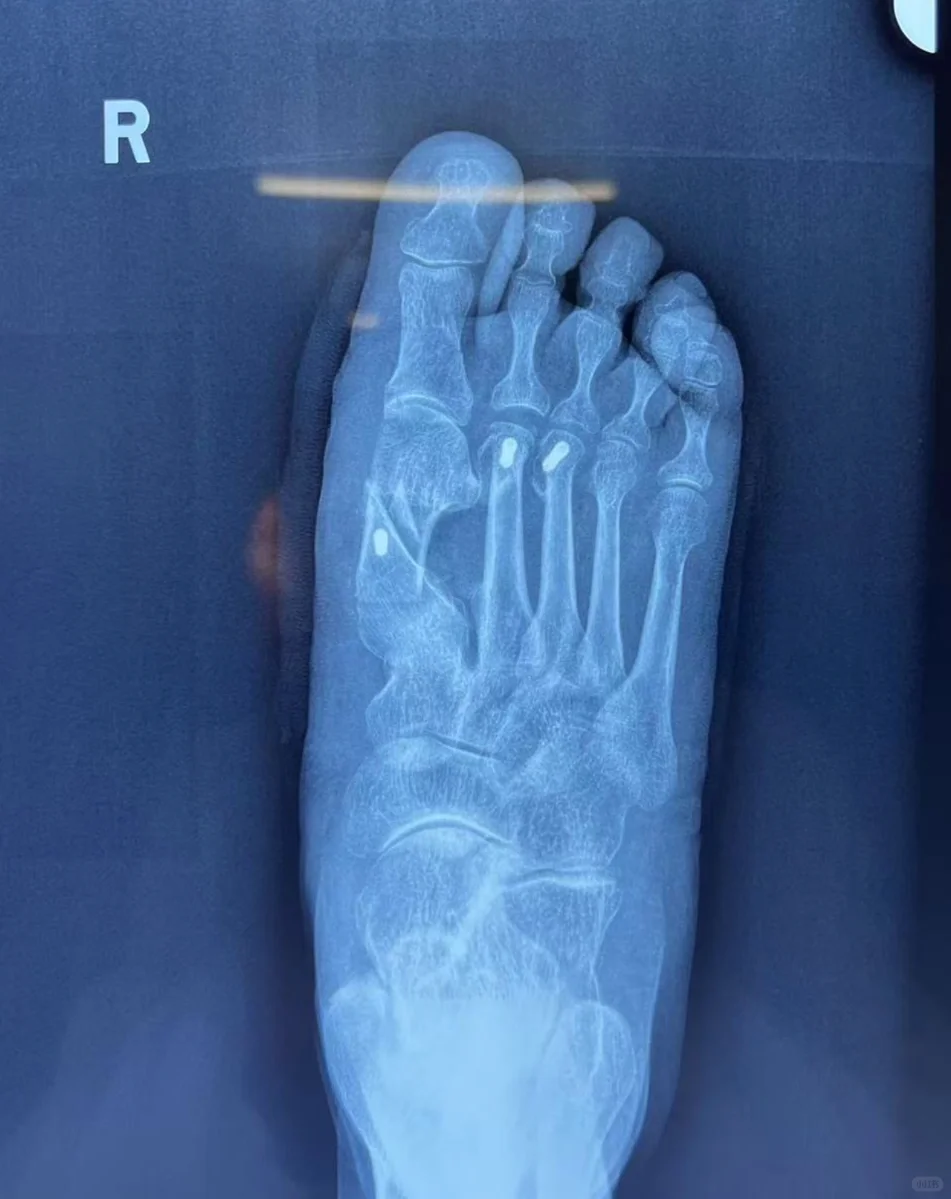

能有一群自己的粉丝,做出拿手的作品与大家品茗欣赏。给自己圈子里的成员做出世上最美好最顶级的作品,在掌声中继续下一个作品。一盘菜,一双脚其实都是艺术品。在信息爆炸的网络世界,最好最优的作品就在我这里!欧克了,人生完美了。